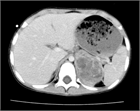

1. 神経芽腫の診断および治療は、小児腫瘍の診療に習熟した小児科医、小児外科医、病理医、放射線科医の協力のもとで行われるべきである(推奨度1)

1. 神経芽腫の予後因子として、病期分類、発症年齢、病理分類、腫瘍細胞の生物学的特性が重要である(推奨度1)